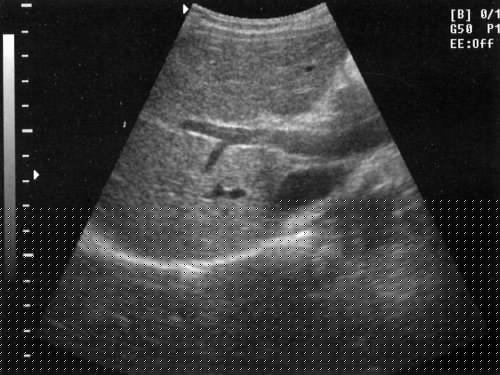

Продольный срез печени

Плотно устанавливаем датчик на кожу под мечевидный отросток и направляем его вверх (рис. 7), затем смещаем в латеральном направлении (параллельно исходной позиции) так, чтобы осмотреть всю печень (рис. 8). Этот срез идеален для исследования левой доли печени.

Рис. 7. Продольное сканирование печени — схема наложения датчика. Следует поддерживать плотный контакт датчика с кожей.

Рис. 8. Эхограммы продольного среза печени.а) Продольный срез печени через правую долю.б) Продольный срез печени через левую долю.